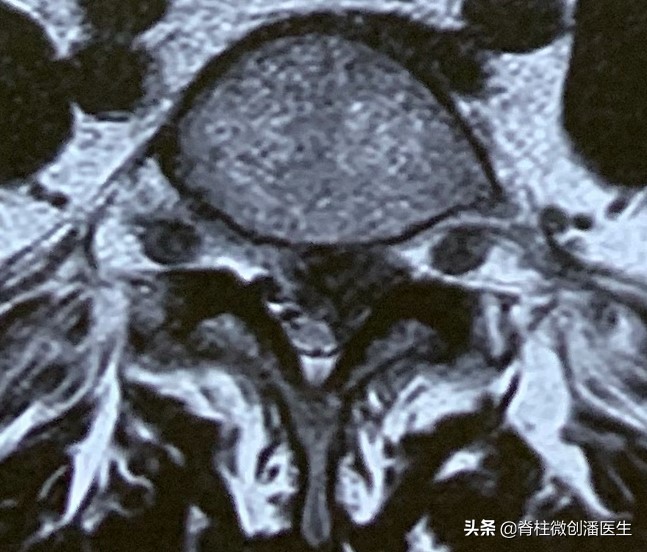

如果在影像学上发现有以下五种征象,往往提示为椎间盘脱出,甚至为游离脱出。

1、低信号的纤维环边缘连续性中断。

2、椎间盘突出物所占椎管的面积在任一截面上(通常为矢状面)上大于50%。